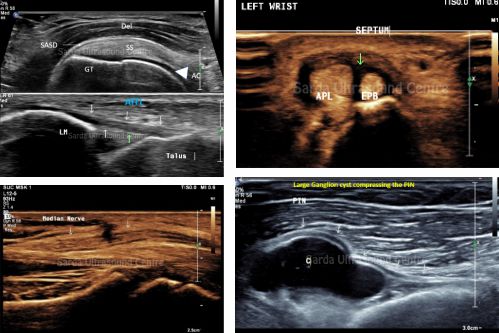

For all these years MRI was the only reliable option for musculoskeletal pathologies. However, with advanced imaging capabilities and high-frequency transducers, we specialize in assessing musculoskeletal disorders, including tendinopathies, Ligament injuries, nerve entrapment, soft tissue masses and many more conditions.

With experience and specialized training in MSK ultrasound, we assure to perform detailed and accurate MSK ultrasound exams to guide treatment planning. We also offer Ultrasound guided MSK interventions which increase the accuracy of injection significantly.

High frequency transducers have revolutionised the way we can visualise the structure of Peripheral nerves in upper and lower limbs. They can be evaluated for various pathologies like compression neuropathy, Post traumatic workup, masses, neuritis and other structural abnormalities with high sensitivity and specificity.